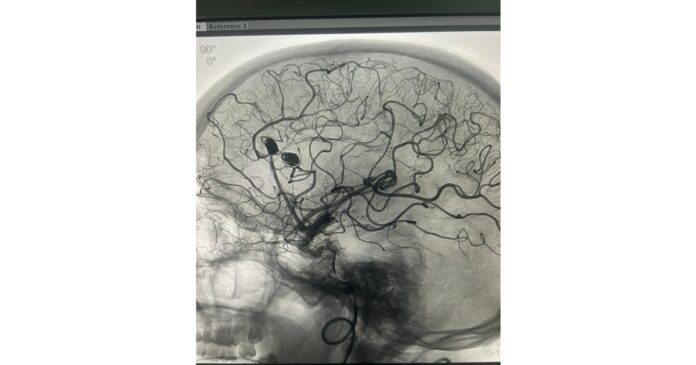

The patient, a 53-year-old male with a history of diabetes and hypertension, arrived at Eternal Hospital with three distal ACA aneurysms, including the pericallosal branch. Complicating matters further, the patient also experienced a corpus callosal bleed with intraventricular extension. The situation demanded immediate attention and expertise to save the patient’s life.

In an extraordinary display of skill and coordination, the multidisciplinary team at Eternal Hospital successfully performed the coiling procedure in a single sitting for all three aneurysms. Utilizing the state-of-the-art facilities of the cathlab, the team overcame the challenges posed by the two aneurysms sharing a common neck, ensuring complete treatment without the need for open brain surgery.